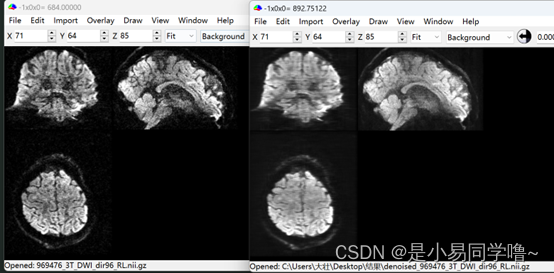

可以看到原图中很多黑点被去除

本实验成功展示了Noise2Noise方法在处理同一b值下不同梯度方向的DWI图像时的高效性和有效性。通过自监督学习,我们不仅绕过了对无噪声图像的需求,而且提升了DWI图像的信噪比,为后续的临床分析和科研探索提供了更为准确和可靠的图像资源。